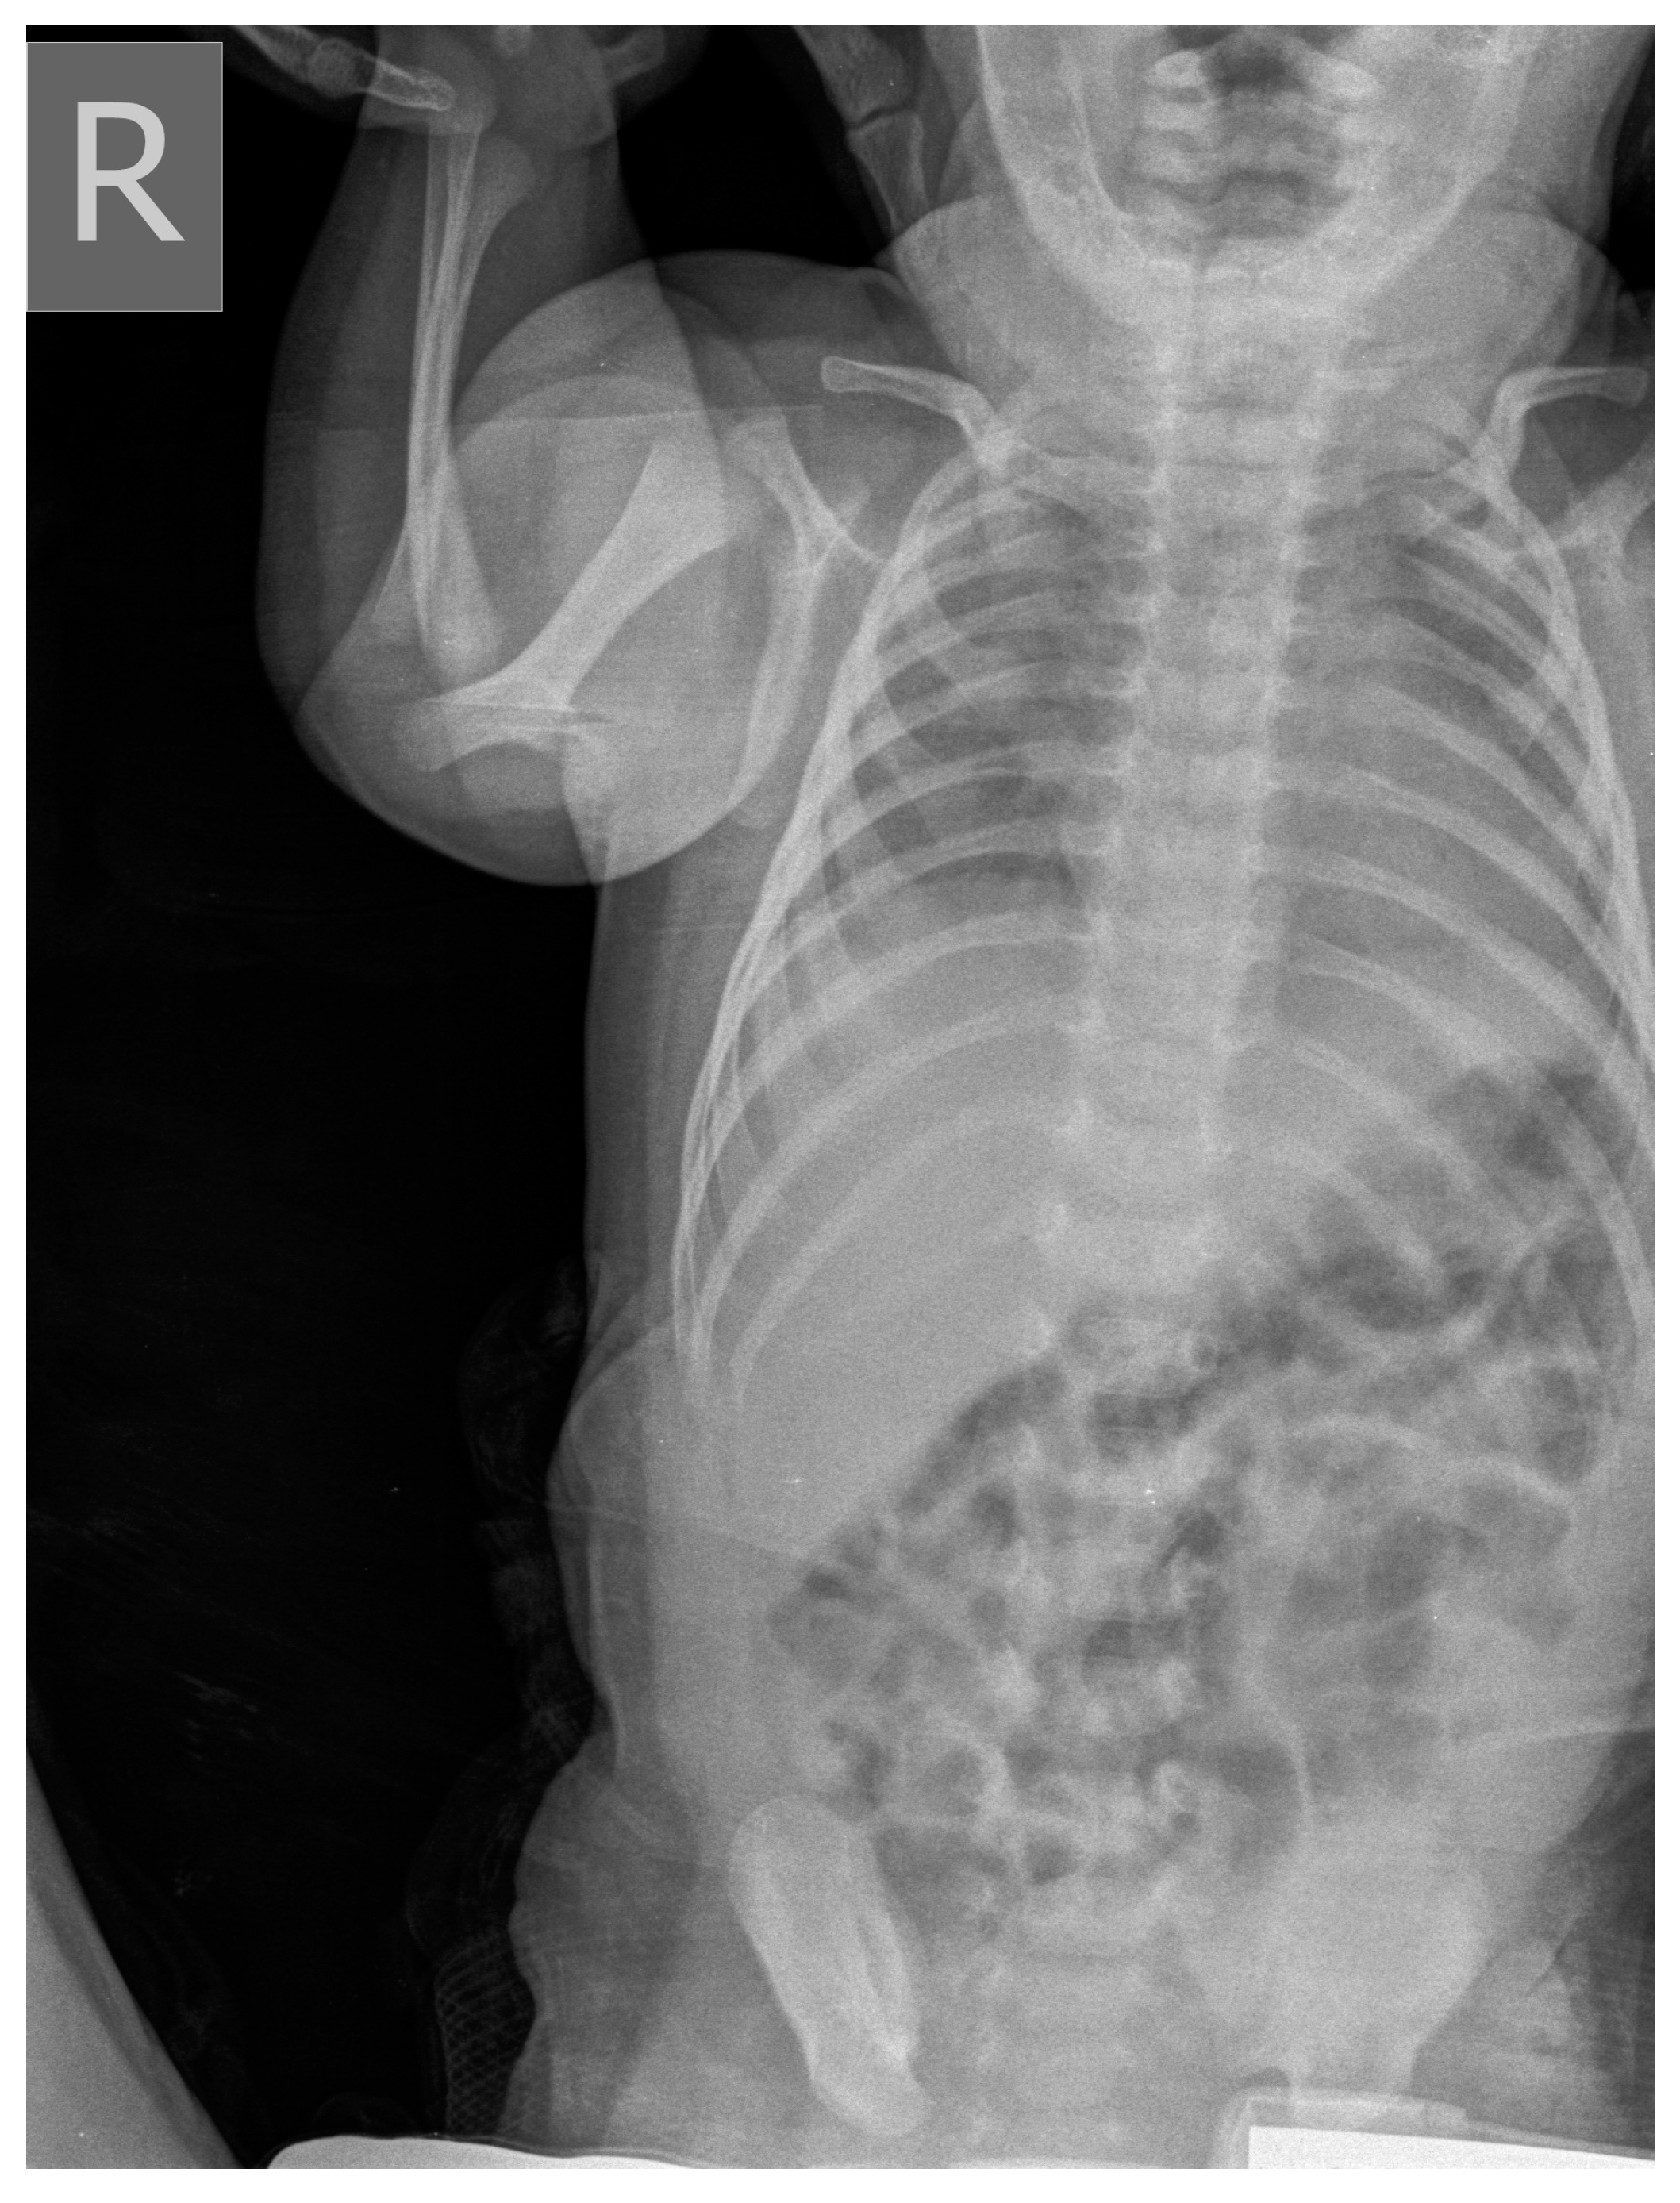

2. Commentary